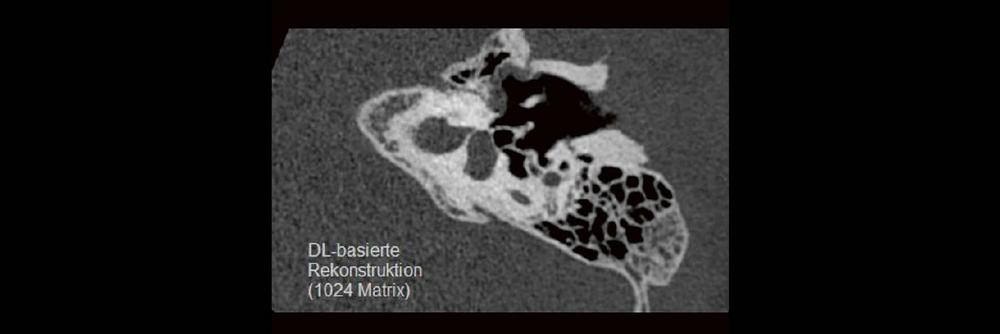

DEEP-Learning-Rekonstruktion in der Neuroradiologie (Webinar | Online)

Professor Dr. med. Marc Brockmann WEITERENTWICKLUNGEN VON KOPF BIS FUSS BEIM VC Oberstarzt Dr. med. Stephan Waldeck DEEP-LEARNING-REKONSTRUKTION IN DER NEURORADIOLOGIE Die CT ist ein […]